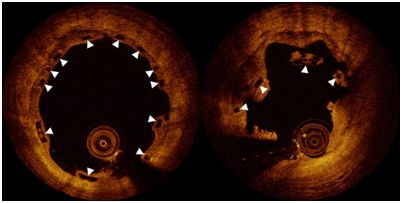

起初,人们并不清楚并发症为何会出现。如今,这些研究人员在心脏病科医师LorenzRäber.教授的领导下,发现了这种原因。他们与欧洲和亚洲的大学合作研究了36名在接受植入一1年多之后遭受生物支架堵塞的患者。这种原因仅通过被称作光学相干断层成像术(opticalcoherencetomography)的高分辨率成像技术才是可检测到的。这种技术提供来自被阻断的生物支架内部的近似显微图片。

Räber说,“这些发现是令人吃惊的。尽管生物支架被正确地植入,但是我们意识到支架片段会侵入冠状血管内部。”事实上,这种生物支架的作用符合设计目标:它分解为单个片段。“然而,如果这些片段不能够完全地进入到冠状动脉血管壁,那么它们能够进入血液中,潜在地导致危险的血凝块形成,随后导致心脏病发作。”